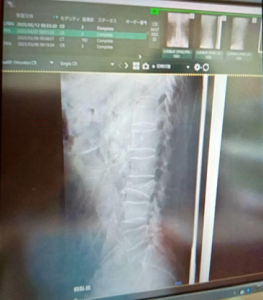

● 3月17日(整形外科・CT)

• ここで初めて「腰椎3番の圧迫骨折」確定診断

• 治癒まで約3ヶ月と説明

• コルセット処方